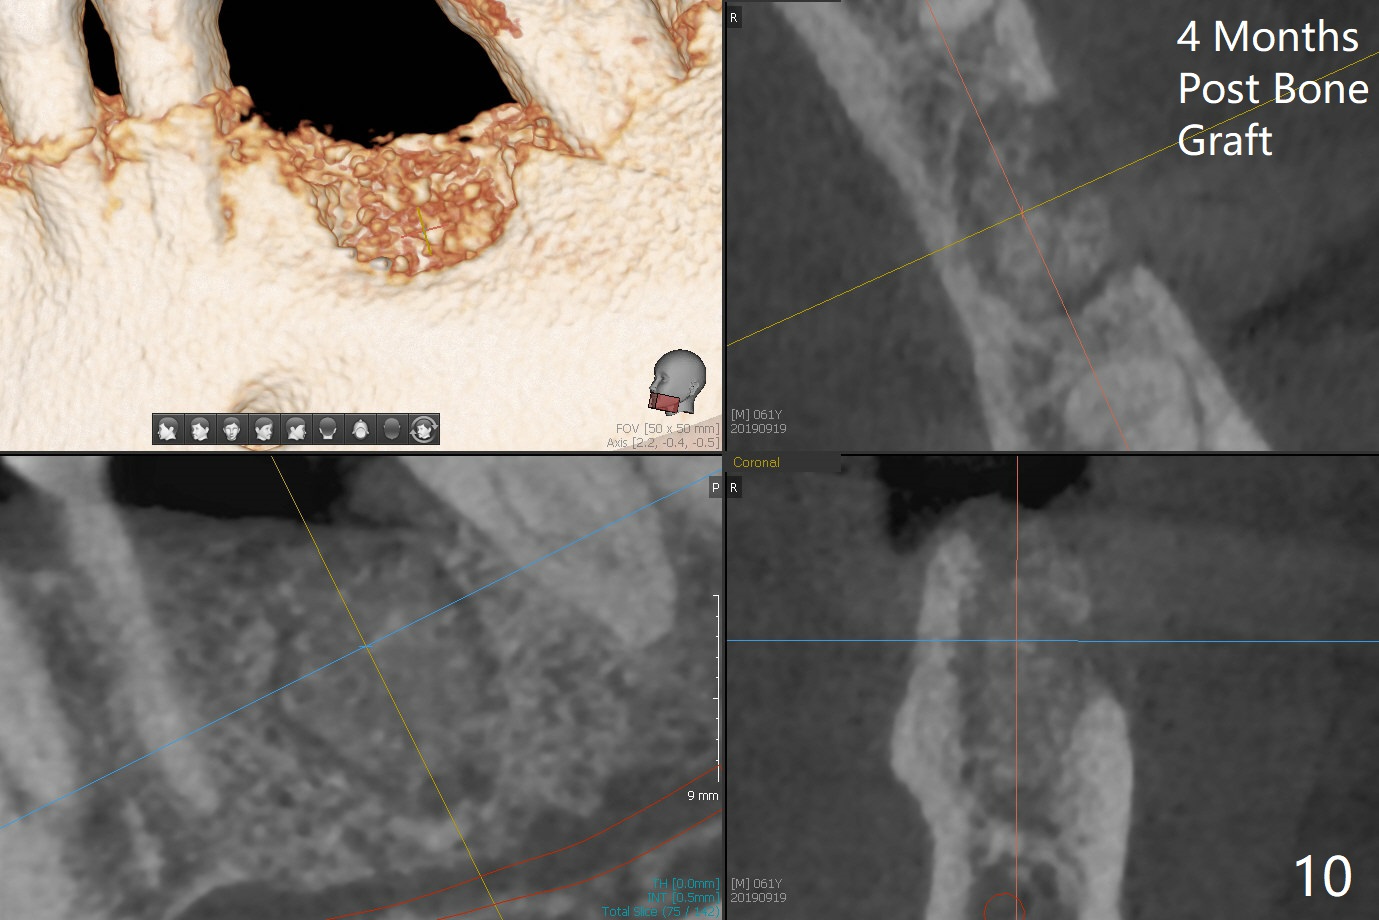

Bone Density Post Extraction with or without Bone Graft

Septum

Critical Area